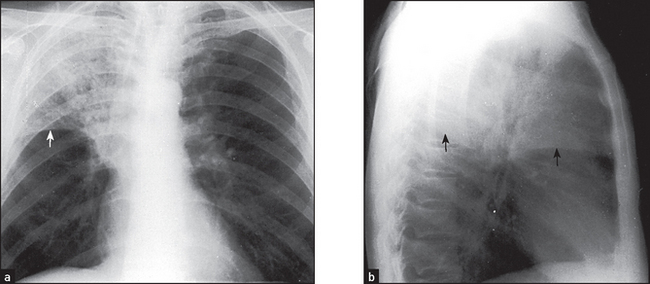

Figure 12.5 (a) and (b) Right upper lobe consolidation The right upper lobe is opacified and is limited inferiorly by the horizontal fissure (arrows). There must be some collapse as well, as the fissure shows some elevation. These changes could be due to a bacterial lobar pneumonia per se, but a central bronchostenotic lesion should be considered. If the pneumonia persists, a bronchoscopy is indicated to search for a central carcinoma.